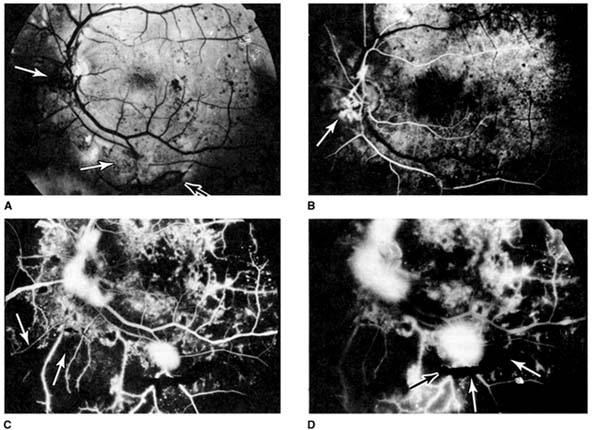

A high-speed motorized film advance allows for rapid sequence photography of the dye's transit through the retinal and choroidal circulations over time. A fluorescein study or "angiogram" therefore consists of multiple black and white photos of the fundi taken at different times following dye injection (Figure 2-29). Early phase photos document the dye's initial rapid, sequential perfusion of the choroid, the retinal arteries, and the retinal veins. Later phase photos may, for example, demonstrate the gradual, delayed leakage of dye from abnormal vessels. This extravascular dye-stained edema fluid will persist long after the intravascular fluorescein has exited the eye.

Figure 2-29

Figure 2-29: Fluorescein angiographic study of an eye with proliferative diabetic retinopathy demonstrating variations in the dye pattern over several minutes' time. A: Fundus photograph of left eye (before fluorescein) showing neovascularization (abnormal new vessels) on the disk and inferior to the macula (arrows). This latter area has bled, producing the arcuate preretinal hemorrhage at the bottom of the photo (open arrow). B: Early phase angiogram of the same eye, in which fluorescein has initially filled the arterioles and highlighted the area of the disk neovascularization. C: Midphase angiogram of the same eye in which dye has begun to leak out of the hyperpermeable areas of neovascularization. In addition to the irregular venous caliber and the microaneurysms (white dots), extensive areas of ischemia are apparent by virtue of the gross absence of vessels (and therefore dye) in many areas (see arrows). D: Late-phase photo demonstrating increasing amounts of dye leakage over time. Although the preretinal hemorrhage does not stain with dye, it is detectable as a solid black area since it obscures all underlying fluorescence (arrows). (Photos courtesy of University of California, San Francisco.)

Figure 2-29 illustrates several of the retinal vascular abnormalities that are well demonstrated by fluorescein angiography. The dye delineates structural vascular alterations, such as aneurysms or neovascularization. Changes in blood flow such as ischemia and vascular occlusion are seen as an interruption of the normal perfusion pattern. Abnormal vascular permeability is seen as a leaking cloud of dye-stained edema fluid increasing over time. Hemorrhage does not stain with dye but rather appears as a dark, sharply demarcated void. This is due to blockage and obscuration of the underlying background fluorescence.